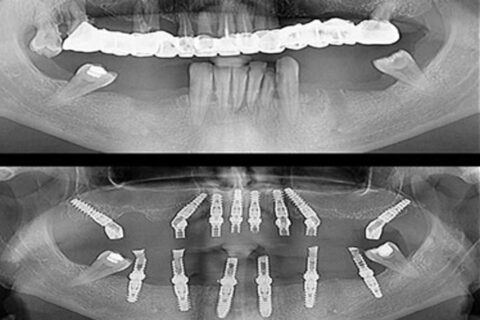

Zygomatic implants, also known as Zygoma implants, are an alternative to bone grafting techniques for the upper jaw and offer a viable option for individuals who desire dental implants but are severely deficient in upper jaw bone. These implants are inserted into the zygomatic bone (cheekbone) to support dentures, bridges, and upper jaw (maxillary) teeth, in contrast to traditional “root form” dental implants that are implanted into the jaws to replace teeth.

They pass transversely through the weak area of the upper jaw and attach to the bottom of the cheekbones via your sinuses.